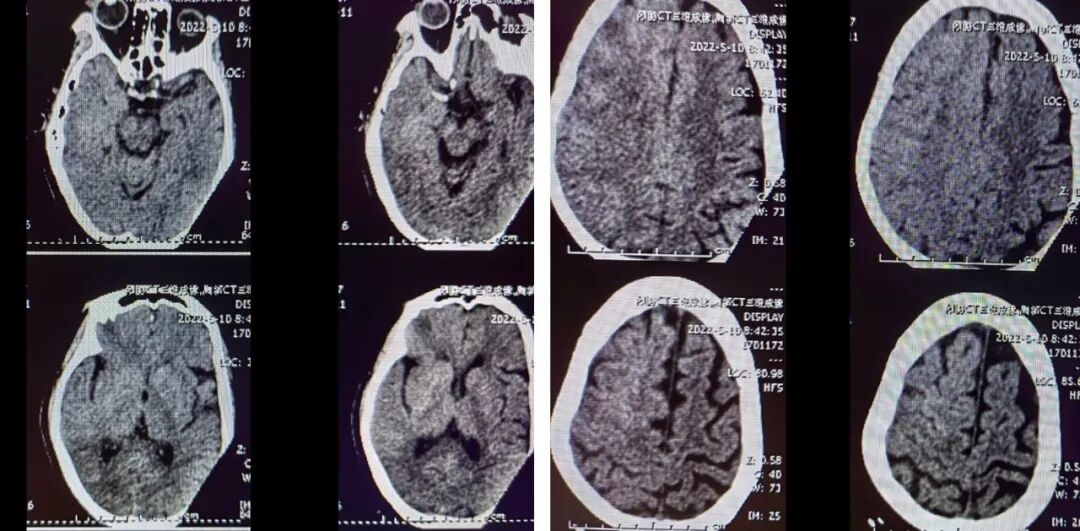

术后影像及随访

(术后8h CT)右侧放射冠区、右侧基底节区、右侧额叶多发急性梗死。

(术后7d CT)右侧放射冠区、右侧基底节区、右侧颞叶、额叶多发急性梗死。